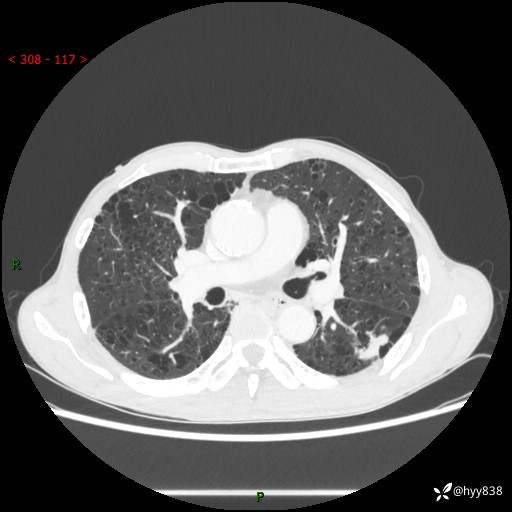

73岁/男,发现肺占位1月余。肺气肿背景,是否恶性倾向---结果公布~

现病史:患者于1月余前无明显诱因出现背部疼痛不适,无明显咳嗽、咳痰、胸闷、咯血、发热等不适,后于2024.5.3至当地市人民医院行胸部CT示:左肺下叶结块,大小约2.2cm*2.6cm,双肺多发小结节,双肺感染性病变,部分纤维增值灶,慢支并双肺局限性肺气肿,肺大泡,纵隔淋巴结增大并部分钙化,冠脉区及大血管壁钙化,双侧胸膜局限性增厚;后口服莫西沙星2周。2024.6.12复查胸部CT示:左肺下叶结块影形态较前饱满,较大截面范围约2.8cm*2.3cm,边缘可见细短毛刺及分叶,性质待查。现患者为求进一步诊治来我院,门诊以“肺占位”收入我科。 起病来,患者精神、食欲、睡眠尚可,大小便正常,体力体重轻微下降。

胸部CT平扫+增强

各期CT值:48hu 100hu 78hu